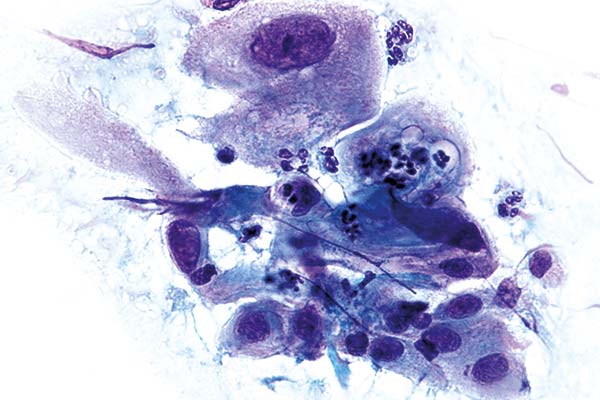

Oktober

richtige Antwort:

e. Strahlenreaktion, Gruppe II-p

- Vakuolisierung des Zellplasmas

- Größenzuname der Zellen durch gestörte Zellteilung

- Vereinzelt Deformierung des Zellkerns der durch die Vakuolen an den Zellrand gedrückt wird

- Pseudoeosinophile Anfärbung des Zytolplasmas

- Kernvergrößerung erdt Tage nach der Bestrahlung

- Mehrkernigkeit, jedoch feinkörniges Kernplasma

- Keine Verschiebung der Kern-Plasma-Relation